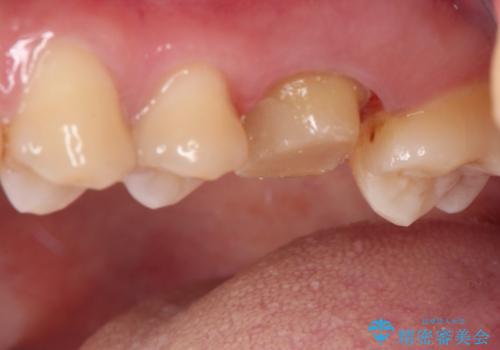

- 矯正治療後に目立つ銀歯を白くしたいとのことで来院された患者様です。

右下の銀の詰め物は、外してむし歯を除去した後、セラミックインレーにて修復することとしました。

左上の銀歯は、銀歯の下に金属の土台が入っているため、その土台を除去し、ファイバーコアにやり替えて、オールセラミッククラウンにて補綴することとしました。